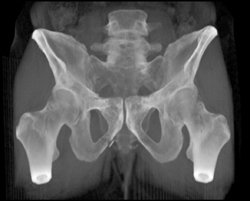

Diagnosis

Cellulitis Dorsum of Foot Seen on CTA